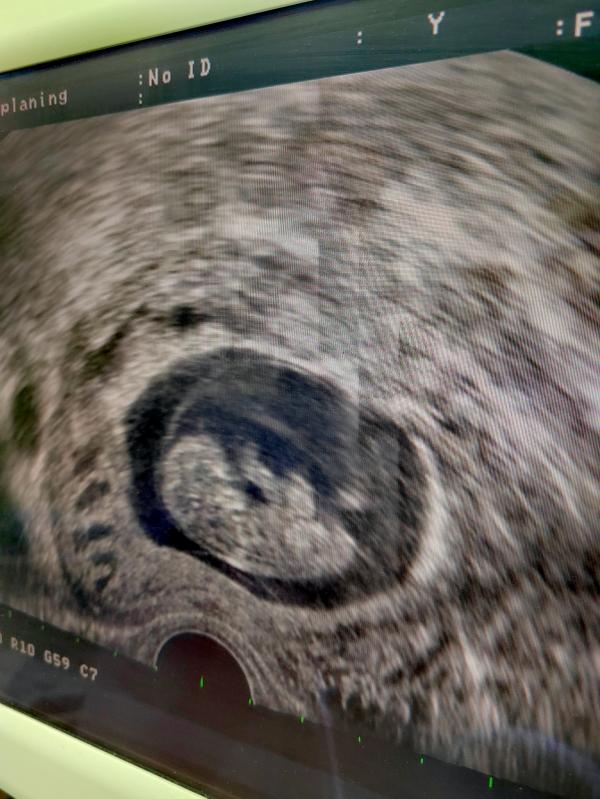

Продолжаю рассказ, об опыте 🤰, без единого признака и ощущений, чтобы другие девочки, у кого так, не пугались. Тк я этим, даже напугала своего репродуктолога😂 и он меня срочно вызвал к себе на узи, тут 10неделек и я впервые увидела, уже не креветку непонятную, а целого человека, с руками ногами и головой, который очень активно там себя презентовал во всей красе. Ни токсикоза, ни чтобы грудь болела, ни спада энергии или гормональных всплесков или странных пищевых пристрастий не было.